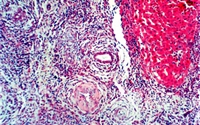

慢性排斥多发生在肝移植术后数月,有报道在移植后*个月就出现,呈渐进性加重,肝功能逐渐恶化,一般呈不可逆转性改变,是移植后期移植肝丧失功能的主要原因,也是影响患者长期健康存活的主要原因...